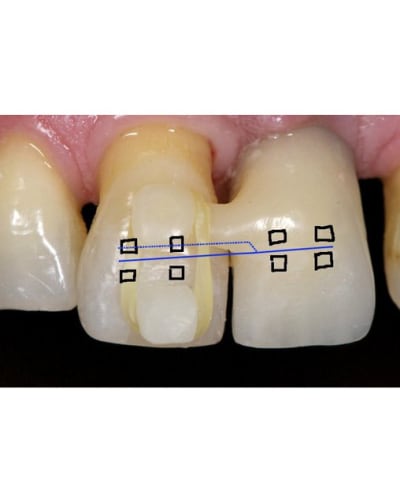

Personnellement j'aurait utiliser deux bracket ou danchemon un sur la provisoire et un sur la 11.

Pour contrôler le mouvement de la 11 avec un fils s'a aurait était plus précis la force aurait était continue aussi.

> Personnellement j'aurait utiliser deux bracket ou danchemon un sur la provisoire

> et un sur la 11.

>

> Pour contrôler le mouvement de la 11 avec un fils s'a aurait était plus précis

> la force aurait était continue aussi.

La tu utilise un implant donc pas besoin de se soucier de la force de réaction. L'implant il ne va pas bouger. Donc un système avec deux brackets et parfaitement gérable au niveau mécanique.

Pour ingresser la dent tu fait juste un pliage du type sur le dessins.

SI la dent procline tu plie le fil en lingual.

Par contre attention vue qu'il s''agit d'un intrusion sur un terrain paro je dirais qu'il ne faut utiliser que des fils de faible diamètre car il ne doivent surtout pas remplir le slot.

Ici il y aurait une très bonne indication pour des danchemon.

Normalement tu dois tout pouvoir faire avec un Niti 0.014.

Ps : sur le shema j'ai mis les bracket en vestibulaire mais il n'y a strictement aucun problème pour les mettre en lingual, mis a part que le pliage devient beaucoup plus délicat.

Mais le gros avantage de coller en lingual ici serait de faire passer la ligne d'action de la force ingressive plus proche du centre de résistance de la 11 et donc de diminuer voir supprimer complètement le mouvement parasite de vestibulo version.

Avec un appuis sur un implant et deux bracket tout devient beaucoup plus simple. Si la dent procline un peut c'est facile a corriger en donnant une pliure en linguale.

Vue qu'un des points d'appuis est immobile le seul élément qui peut bouger c'est la 11 donc très facile de contrôler la position par pliage.